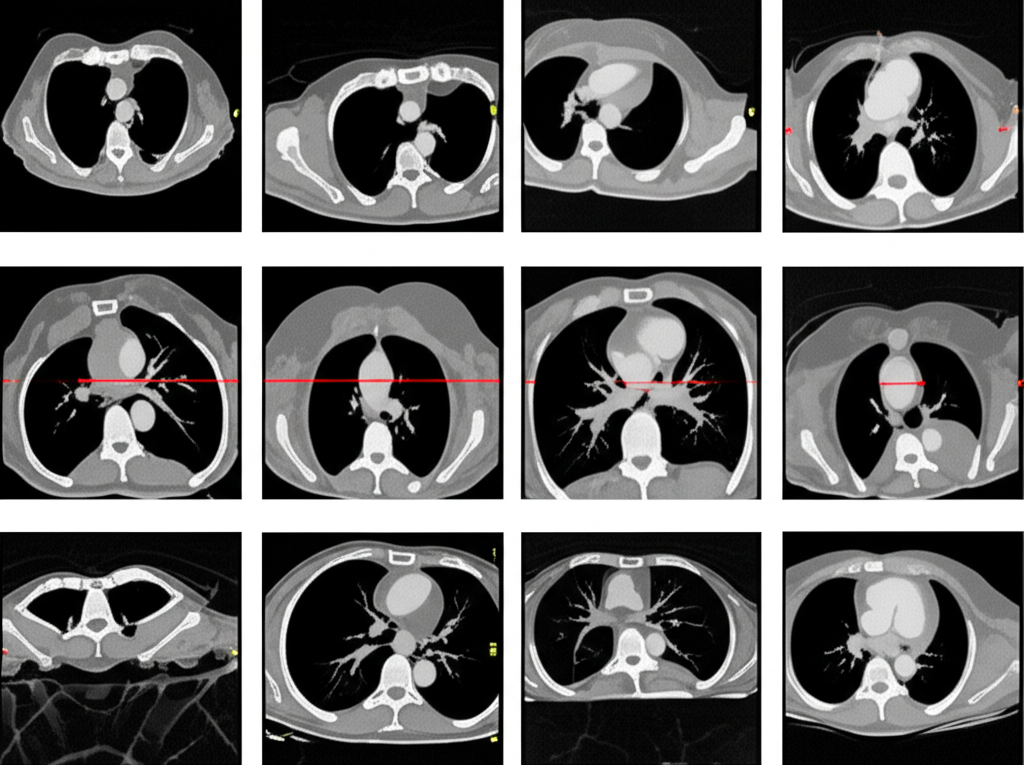

심장 CT(Computed Tomography)는 컴퓨터 단층 촬영 기술을 이용하여 심장의 단면 영상을 얻는 검사입니다. 기존의 엑스레이 촬영보다 훨씬 더 자세하고 정확한 이미지를 제공하여, 심장 질환의 조기 진단과 치료 계획 수립에 큰 도움을 줍니다. 심장 CT는 특히 관상동맥 질환, 심장 판막 질환, 심근 질환 등 다양한 심장 질환을 진단하는 데 유용합니다.

심장 CT 검사를 통해 다음과 같은 다양한 정보를 얻을 수 있습니다.

- 관상동맥 질환 진단: 관상동맥 CT는 관상동맥의 협착이나 폐쇄 여부를 정확하게 진단할 수 있습니다. 특히, 칼슘 스코어링을 통해 동맥경화의 정도를 평가하고, 향후 심혈관 질환 발생 위험을 예측할 수 있습니다.

- 심장 구조 평가: 심장의 크기, 모양, 위치 등을 정확하게 파악하여 심장 비대, 심방중격결손, 심실중격결손 등 선천성 심장 질환이나 심장 구조 이상을 진단할 수 있습니다.

- 심장 기능 평가: 심장의 수축력과 이완력을 평가하여 심부전 진단에 도움을 줄 수 있습니다. 심장 CT는 심장의 각 부위별 기능을 평가하여, 심부전의 원인을 파악하는 데 중요한 정보를 제공합니다.

- 심장 종양 진단: 심장 내 종양의 유무와 크기, 위치 등을 파악하여 종양의 종류와 치료 계획을 결정하는 데 도움을 줄 수 있습니다.

- 심낭 질환 진단: 심낭염, 심낭삼출 등 심낭 질환을 진단하고, 심낭의 두께와 염증 정도를 평가할 수 있습니다.

- 대동맥 질환 진단: 대동맥류, 대동맥 박리 등 대동맥 질환을 진단하고, 대동맥의 크기와 모양을 평가할 수 있습니다.